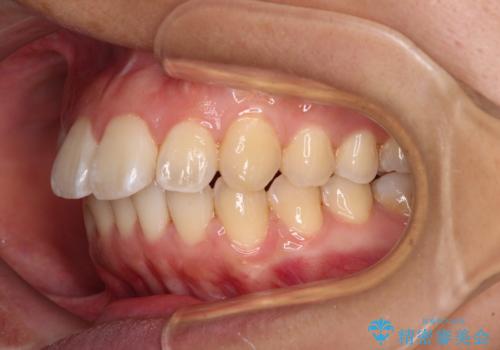

- 前方に傾斜した上下の前歯を気にして来院された患者様です。

唇の閉じにくさや横顔のシルエットが気になるような突出感ではなかったため、インビザラインを用いて、歯列の遠心移動とIPR(歯と歯の間を削る)により前歯の傾斜を改善していくこととしました。

スムーズに終了すると思われましたが、インビザライン矯正独特の奥歯が咬み合わない状態が続き、更には遠方へ転居されたこともあり、治療期間は長引いてしまいました。